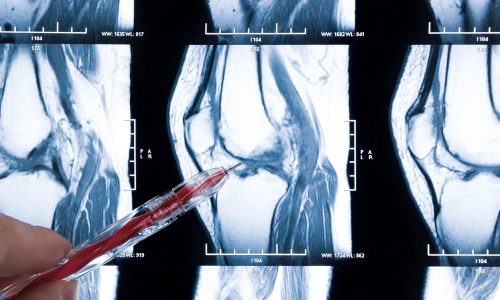

A ruptura horizontal do menisco é uma lesão comum no joelho, especialmente em pessoas que praticam esportes ou apresentam desgaste articular devido ao envelhecimento. Esse tipo de lesão pode causar dor, inchaço e dificuldade na movimentação do joelho, comprometendo a qualidade de vida. Felizmente, existem diversas abordagens para tratar a ruptura, desde tratamentos conservadores até intervenções cirúrgicas. Neste artigo, você conhecerá as principais opções de tratamento e dicas para uma recuperação eficaz.

O menisco é uma estrutura cartilaginosa localizada entre o fêmur e a tíbia, responsável por absorver impactos e estabilizar o joelho. Quando ocorre uma ruptura horizontal, a lesão se estende paralelamente ao eixo do menisco, podendo afetar sua função e causar desconforto.